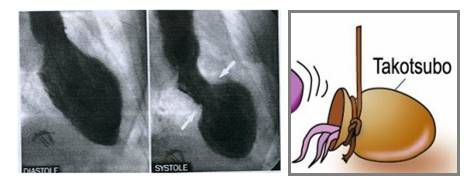

当应激性心肌病遇到了左室流出道梗阻

◆应激性心肌病是指严重精神或躯体应激下出现一过性左室功能障碍的疾病,又称为心尖部球型综合征和章鱼罐心脏

◆应激性心肌病可引起室间隔局限性肥厚,导致左室流出道梗阻,引起二尖瓣前叶收缩期前移和急性二尖瓣反流,导致心源性休克,β受体阻滞剂是治疗和预防左室流出道梗阻的最佳选择